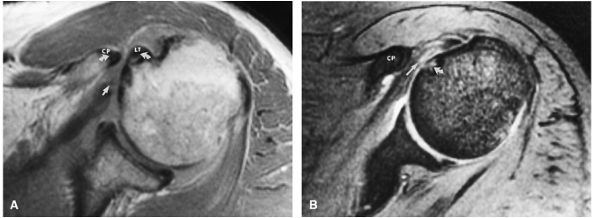

![]() |

FIGURE 8.3 ● Glenohumeral joint contrast on axial T2* GRE image. Axial GRE images optimize visualization of intralabral signal and subscapularis tendinosis. FS FSE images are more sensitive to fluid collections, paralabral cysts, and articular cartilage.

FIGURE 8.4 ● (A) Axial FS PD FSE image shows intact and congruous humeral head and glenoid articular cartilage surfaces (arrows), separate from the high-signal-intensity intra-articular contrast. (B) PD FSE contrast without FS is shown in an axial image of a Bankart lesion. Chondral surfaces are not as well demonstrated. (C) Excellent contrast is shown between the avulsed anterior labrum and the anterior glenoid rim on the corresponding sagittal FS PD FSE image.